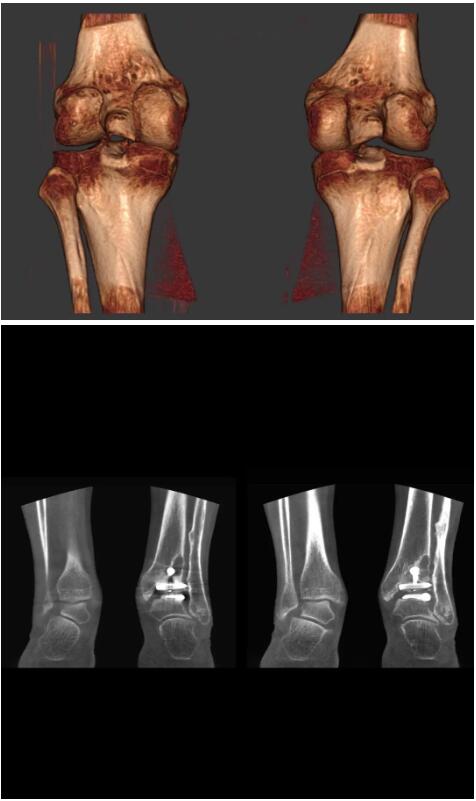

以上介紹的CT均來自國外同一家公司,這些CT均配置了可視化軟件,可以進行切片、3D重建以及大型CT附帶的所有典型的操作功能。

以下是這些“特立獨行”的CT所拍出來的圖像: